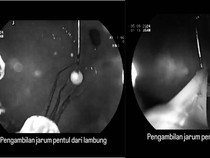

Round Up Detik-detik Dokter Senior FKUI Keluarkan Jarum Pentul dari Lambung Selasa, 17 Sep 2024 06:01 WIB

Jarum Pentul 'Nyangkut' di Lambung saat Pakai Hijab, Begini Wanti-wanti Dokter Senin, 16 Sep 2024 10:02 WIB

Viral Dokter Keluarkan Jarum Pentul dari Lambung, Tertelan saat Pakai Hijab Senin, 16 Sep 2024 08:12 WIB